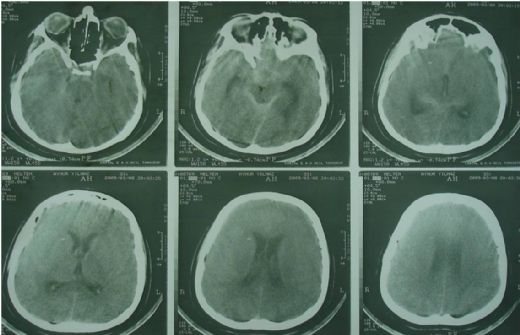

Subdural Kanama Belirtileri Ve TedavisiSubdural kanama, beynin dışındaki zarların arasında kan birikmesi durumunu ifade eder. Genellikle kafa travması sonrası ortaya çıkan bu durum, acil tıbbi müdahale gerektiren ciddi bir sağlık sorunudur. Bu makalede, subdural kanamanın belirtileri, tanı yöntemleri ve tedavi seçenekleri ele alınacaktır. Subdural Kanama Nedir? Subdural kanama, beyin zarı (dura mater) ile beyin arasındaki boşlukta kan birikmesiyle oluşur. Bu durum, genellikle kafa travması sonucu meydana gelir ancak bazı durumlarda, kan damarlarının zayıflaması veya çeşitli hastalıklar da subdural kanamaya yol açabilir. Subdural Kanamanın Belirtileri Subdural kanamanın belirtileri, kanamanın şiddetine ve süresine bağlı olarak değişiklik gösterebilir. Genel olarak, aşağıdaki belirtiler gözlemlenebilir:

Bu belirtiler, subdural kanamanın acil bir durum olduğunu gösterir ve derhal tıbbi yardım alınması gerektiğini ifade eder. Tanı Yöntemleri Subdural kanamanın tanısı genellikle aşağıdaki yöntemlerle konulur:

Tedavi Seçenekleri Subdural kanamanın tedavisi, kanamanın boyutuna, nedenine ve hastanın genel sağlık durumuna bağlı olarak değişir. Tedavi yöntemleri şunlardır:

Sonuç Subdural kanama, acil bir durum olup, belirtilerinin fark edilmesi ve hızlı bir şekilde tıbbi müdahale yapılması hayati önem taşır. Erken tanı ve tedavi, hastanın iyileşme sürecini olumlu yönde etkiler. Bu nedenle, kafa travması geçiren bireylerde belirtilerin gözlemlenmesi ve gerekli tetkiklerin yapılması önem arz etmektedir. Ek Bilgiler Bu makale, subdural kanamanın belirtileri ve tedavi yöntemleri hakkında genel bir bilgi sunmayı amaçlamaktadır. Herhangi bir sağlık sorunu durumunda mutlaka bir sağlık profesyoneline başvurulması gerektiği unutulmamalıdır. |